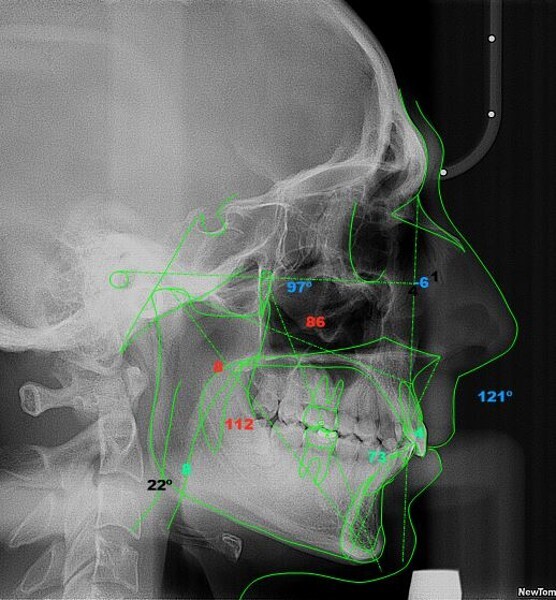

Four years after this case had been completed, the patient came for a review, and both radiographic and photographic records were taken to evaluate any changes that may have occurred over this retention period (Figs. 26–30). Cephalometric analysis was performed again and the results compared with the immediate post-treatment results (Table 2).

The radiographic equipment used on this occasion was not the same as we had used before, so the results obtained should not be considered totally accurate. Despite this setback, the patient’s status remained significantly better than at the beginning of treatment, since the patient still had a Class I occlusion, his profile was harmonious, and most notably, he was still satisfied with the results.

Table 2: Comparison of the changes that occurred during the orthodontic treatment (pretreatment, post-treatment and retention) according to cephalometric analysis.

Analysis approach Comparison of cephalometric results

Steiner Angle/line Pretreatment Post-treatment Retention

SNA angle 81° 82° 80°

SNB angle 74° 74° 75°

ANB angle

XY axis angle 73° 74° 73°

Wits 8.3° 7.2° 2.0°

Maxillary incisor position 6.9° -0.2° 3.6°

Mandibular incisor position 8.0° 9.5° 8.7°

Inter-incisal angle 118° 121° 121°

Maxillary incisor angle 28° 15° 17°

Mandibular incisor angle 27° 35° 36°

Ricketts Facial axis 84° 84° 83°

Mandibular incisor protrusion 0.9 mm 1.6 mm 4.0 mm

Mandibular incisor inclination 22° 27° 33°

Labial protrusion 1.5 mm 0.8 mm -6.2 mm

McNamara Maxillary length 91.0 mm 92.0 mm 85.6 mm

Mandibular length 111.9 mm 113.3 mm 112.3 mm

Maxillomandibular difference 20.9 mm 19.3 mm 26.8 mm

Lower anterior facial height 73.9 mm 74.9 mm 73.4 mm